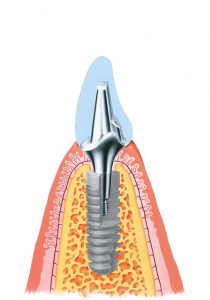

Дентальные имплантаты – это своеобразные «искусственные корни». Они устанавливаются в костную структуру челюстей после её трепанации (в случае отсроченной имплантации).

Как было сказано зубной имплантат вкручивается не в корень зуба, как в случае со штифтовыми конструкциями. Имплантат вкручивается в кость, в проекции отсутствующей зубной единицы. Имплантат имеет вид стержня конусовидной формы, на него нанесена резьба, и изготовлен он из металла. Материалом изготовления чаще всего выступает титан. Этот материал обладает хорошей биосовместимостью с тканями организма и не даёт аллергических реакций.

Как было сказано зубной имплантат вкручивается не в корень зуба, как в случае со штифтовыми конструкциями. Имплантат вкручивается в кость, в проекции отсутствующей зубной единицы. Имплантат имеет вид стержня конусовидной формы, на него нанесена резьба, и изготовлен он из металла. Материалом изготовления чаще всего выступает титан. Этот материал обладает хорошей биосовместимостью с тканями организма и не даёт аллергических реакций.

Имплантат может быть разборным и не разборным. В случае неразборной конструкции – это сплошной титановый стержень, который вкручивается в кость и на него фиксируется временная ортопедическая конструкция, а после формирования десневого края временная коронка замещается постоянной.

- Титанового стержня в форме корня.

Разборные имплантаты ещё называют двухэтапными. Процесс их установки проходит несколько этапов. Сначала в кость фиксируют «искусственный корень» с заглушкой и ушивают разрезанную слизистую оболочку. После того как имплантат приживётся, обычно для этого нужно несколько месяцев, снова надрезают слизистую оболочку, удаляют заглушку, а на её место вкручивают формирователь десны. Для того чтобы сформировался десневой контур должно пройти 14 дней, иногда немного больше. После этого формирователь десны извлекают, а на её место фиксируют абатмент, который и будет опорой для искусственной зубной единицы.